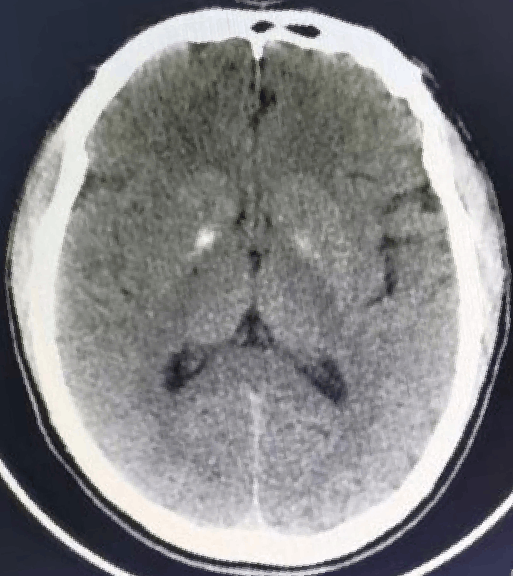

术后随访:

术后MRI

NIHSS评分0分